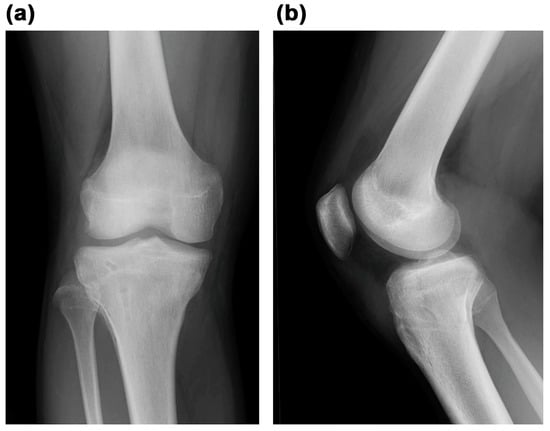

Type V Tibial Tubercle Avulsion Fracture with Suspected Complication of Anterior Cruciate Ligament Injury: A Case Report

2. Case Report